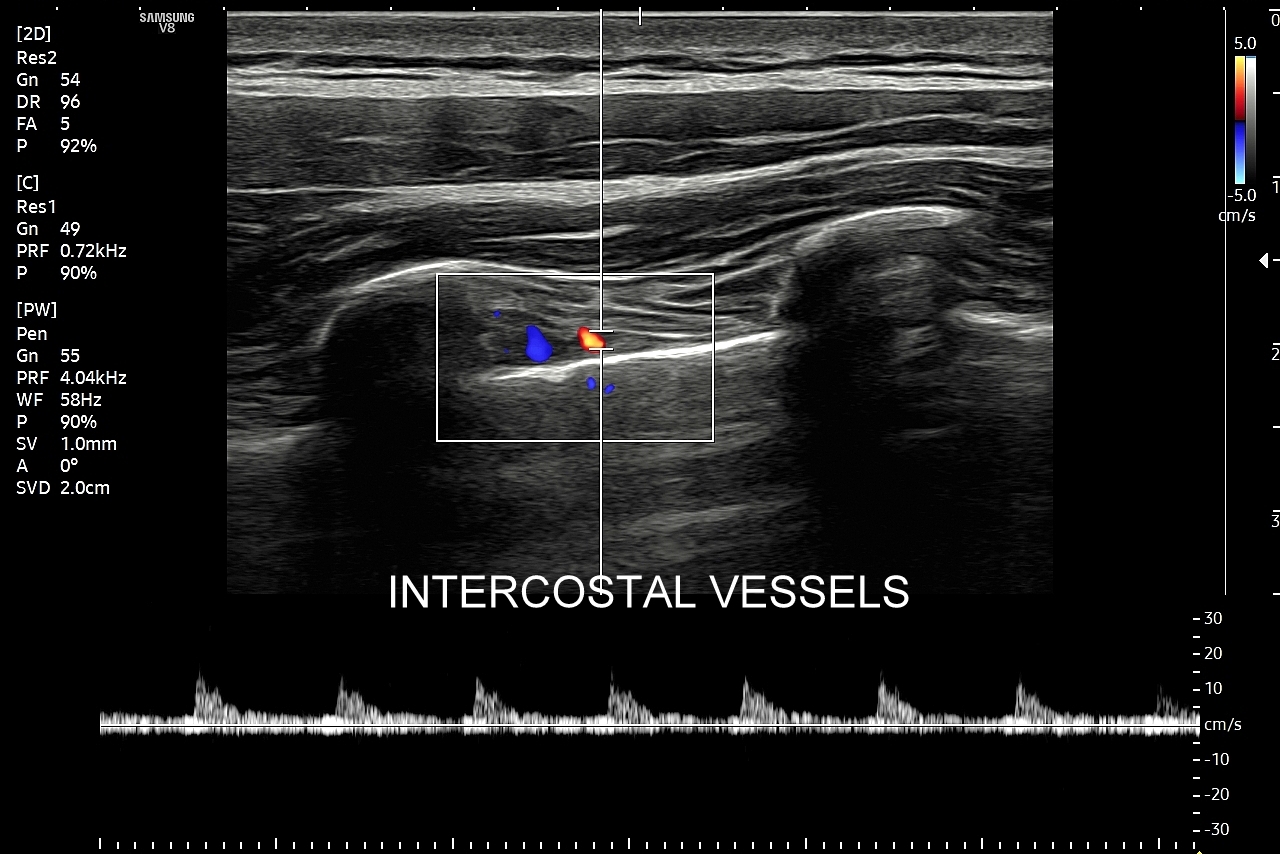

Badanie USG płuc w wybranych przypadkach korzystnie jest połączyć z jednoczesną oceną echokardiograficzną serca oraz dużych naczyń klatki piersiowej, tj. aorty wstępującej i tętnic płucnych. USG układu mięśniowo-szkieletowego klatki piersiowej wykorzystywane jest z kolei w diagnostyce stanów urazowych, takich jak złamanie żeber, czy przeciążenie połączeń chrzęstno-kostnych żeber; w wymienionych przypadkach USG ma wyższą czułość w porównaniu do oceny rentgenowskiej.

Specjalista chorób wewnętrznych. Absolwent Akademii Medycznej we Wrocławiu w 2000 r. Zwolennik nowoczesnych technologii i pionier niestandardowych zastosowań USG w Polsce, w tym użycia obrazowania mikroprzepływów w obrazowaniu płuc, czy badań USG z kontrastem. Na początku lat 2000-ych był jednym z pierwszych lekarzy, który wdrażali szerokie zastosowanie USG w intensywnej terapii. W praktyce ambulatoryjnej wprowadził do regularnego użycia kompleksowe badanie USG klatki piersiowej, płuc i serca. Posiada wieloletni staż kliniczny i szkoleniowy w Polsce oraz zagranicą (Wielka Brytania, Niemcy, Austria, Włochy, Rumunia). Wykonał ponad 40.000 badań USG. Dydaktyk i nauczyciel młodego pokolenia lekarzy w Polsce i Europie.